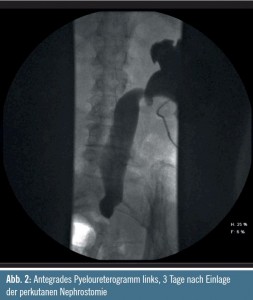

Es wurde eine perkutane Nephrostomie links eingelegt. Im Anschluss daran verbesserten sich die Werte für Serumkreatinin und Harnstoff langsam, das Serumkreatinin blieb schlussendlich bei 120 µg/ml. Ein CT-Abdomen mit oralem Kontrastmittel (Abb. 1) und ein antegrades Pyelogramm (Abb. 2) wurden durchgeführt. Weitere Pathologien außerhalb des Harntraktes wurden vom Radiologen im CT nicht beschrieben.

Das CT-Abdomen mit oralem Kontrastmittel (Abb. 1) ist ungenügend für die Stadieneinteilung. Die Obstruktion im distalen Harnleiter ist am wahrscheinlichsten durch eine Lymphangiosis carcinomatosa verursacht – oft durch konventionelle Bildgebung nicht darstellbar. Da der Metastasierungsweg des Zervixkarzinoms entlang der Lymphbahnen (iliakal, obturatorisch, retroperitoneal, mediastinal) und in die Lunge erfolgt, ist ein 18F-Fluorodeoxyglukose-PET-CT zu empfehlen.